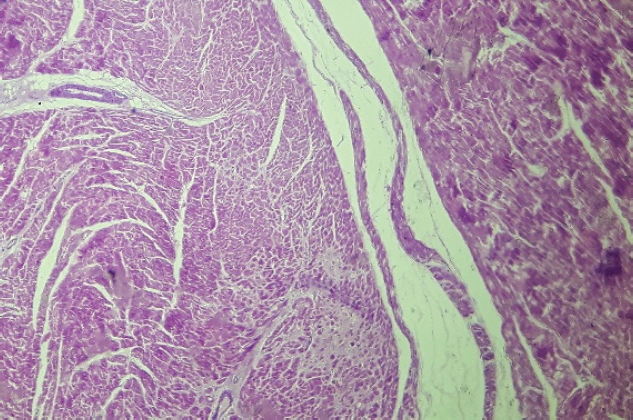

After 24 Holter monitoring, the patient died suddenly during physical activity. Permission for conducting necropsy was obtained from the animal owners. Postmortem examination showed marked cardiomegaly (heart weight bigger than 13 g/kg body weight). No lung edema, pleural effusion or ascites were observed. The heart was explanted and preserved in 10% formalin and then sent for examination to the pathology service of the Hospital Santojani (Buenos Aires), where fragments from both ventricles and the septum were processed with the routine technique to make paraffin-embedded blocks. 4 μm thick sections were cut and stained with hematoxylin-eosin (H&E). Adipose and fibroadipose replacement of the right ventricle free wall of up to 50% of its thickness was observed. These lesions had a predominantly subepicardial distribution. Subepicardial fibroadipose replacement of the left ventricle with involvement of the septum was also observed (Fig. 3). In addition, adipose tissue was also observed in the left ventricle, affecting the base of implantation of the papillary muscles at the septum (Fig. 4). In areas of the left ventricle, co-existence of perivascular fibrosis, myocardial fibrosis suggestive of previous necrosis, and interstitial fibrosis were detected (Fig. 5). In addition, wavy fibers in the myocardium in both ventricles were observed. Clusters of myocardial fibers were also observed within all areas of adipose tissue deposition.

Fig. 4. Base of the left ventricle papillary muscle (H&E, 100×). Histopathological image showing presence of adipose tissue at the base of the papillary muscle.